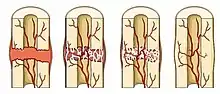

The bones of a child are more likely to bend than to break completely because they are softer and the periosteum is stronger and thicker.[3] The fractures that are most common in children are the incomplete fractures; these fractures are the greenstick and torus or buckle fractures.

Greenstick fracture

This fracture involves a bend on one side of the bone and a partial fracture on the other side. The name is by analogy with green (i.e., fresh) wood which similarly breaks on the outside when bent. The Sub-nanostructure of cortical bone may provide one possible explanation for the greenstick fractures in children. On the contrary to adults bone tissue, the low ratio between the mature and the immature enzymatic cross-links in children bone tissue is a potential explanation of the presence of greenstick fractures in children.[5]